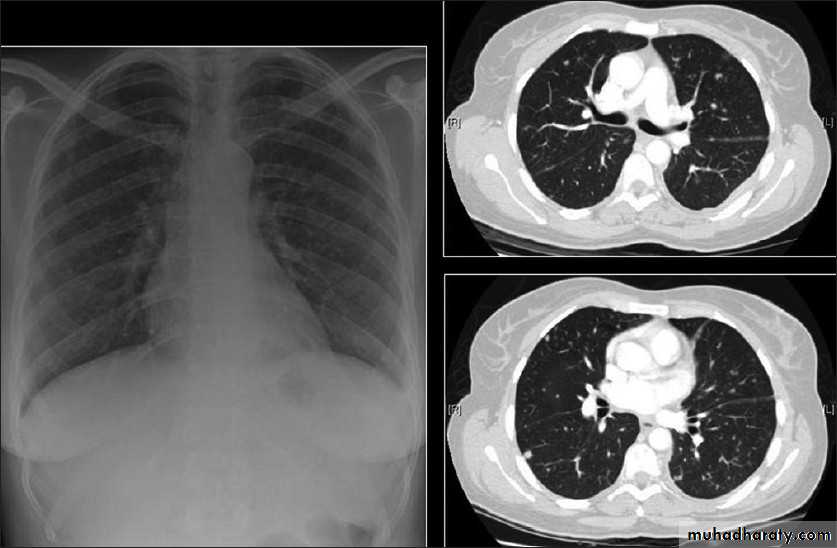

High resolution CT (HRCT) can be helpful in minimizing the differential diagnosis:

• Focal opacification favours bacteria, mycobacteria and nocardia

• Bilateral opacification favours PCP, fungi, viruses and nocardia

• Cavitation suggest mycobacteria, fungi and nocardia

• Pleural effusion suggests bacteria